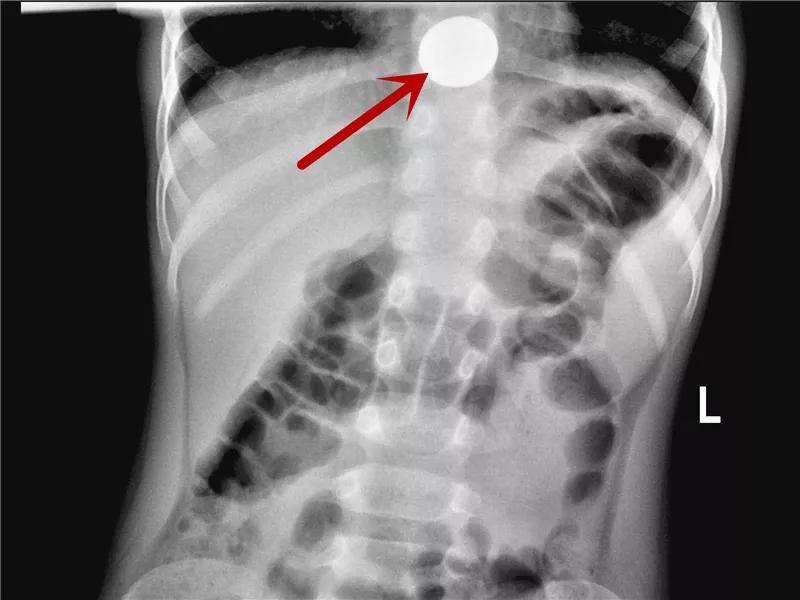

硬币的一场“旅行”

硬币是儿童消化道异物中最最最常见的。虽然有些孩子可以自行排出,但是部分幼龄患儿仍需手术取出。家长还是当心点吧!

到达食道最下端,贲门口上方了,只差临门一脚就进入胃了